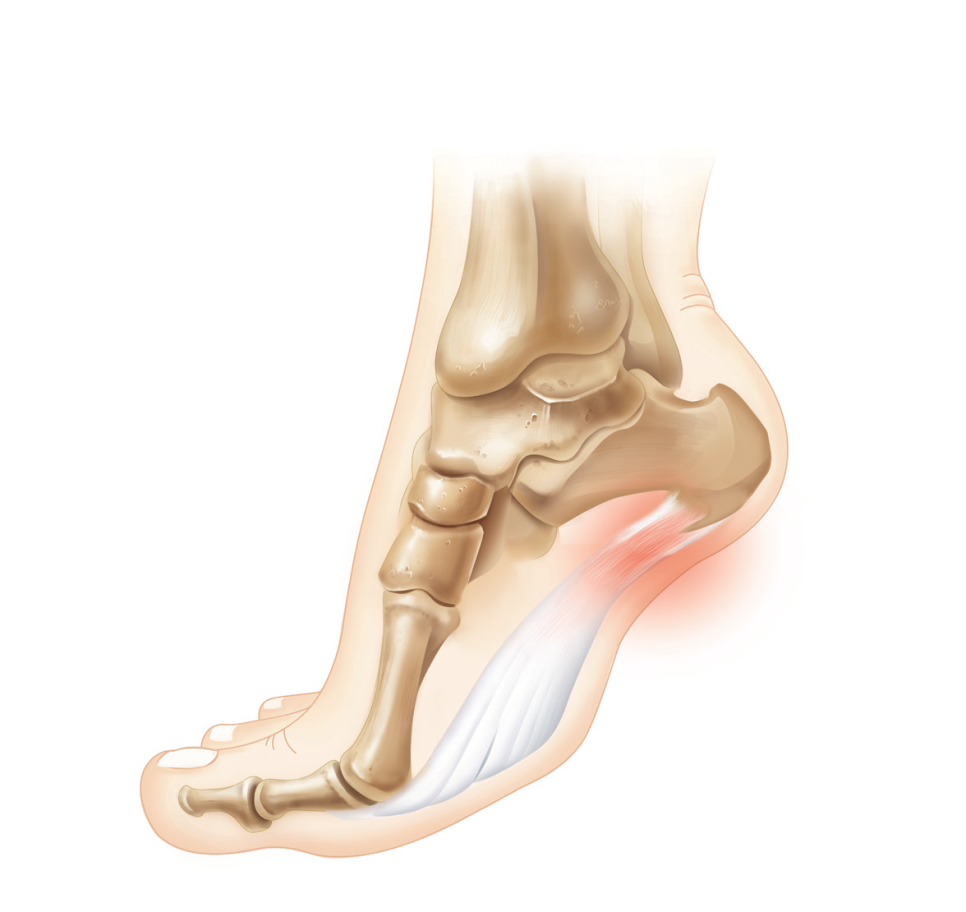

□ 발바닥 근막이 종골 기시부에서 반복적인 미세손상을 입어 발뒤꿈치로 통증이 나타나는 것을 말합니다.

□ 종골의 내측 및 발 안쪽을 따라 발생하는 통증과 압통을 특징으로 합니다.

□ 특히 아침에 일어나 처음 발을 디딜 때 심한 통증이 나타납니다.